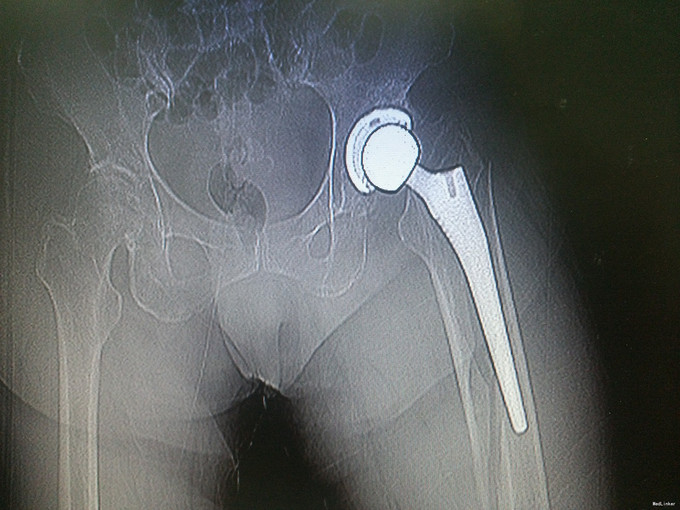

查体:左髋可见一长约8cm的手术疤痕,局部无明显肿胀,左下肢杠力消失,纵向叩击痛(+),肢端血运、感觉及活动良好。 辅助检查:骨盆X片:左股骨假体周围骨折。

诊断:假体周围骨折(左股骨假体柄周围骨折);高血压病;脑梗死后遗症;陈旧性肺结核 治疗:手术治疗[左侧股骨假体取出术+左侧股骨假体周围骨折切开复位钢板钢缆内固定术(zimmer)+左侧股骨假体置入术(MP,Link)] 术中探查及处理:股骨大粗隆崩裂,骨折线自近端向远端延伸至股骨中段,呈螺旋形,骨折块粉碎,移位明显。骨折断端可见淤血块。顺利取出假体柄后,复位骨折块,予复位钳临时固定后,予钢板钢缆(zimmer)加压捆扎。待骨折固定牢靠后,按照髋关节置换流程逐步扩髓,最后选择25omm长的14号假体(MP,Link)安装,36mm标准颈股骨头复位。测试各方向活动良好,松紧度合适。